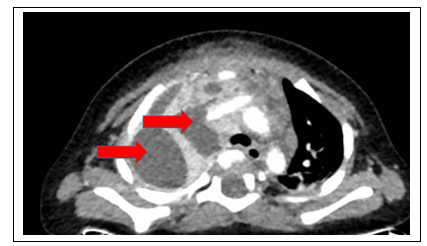

Hình ảnh: CT scan ngực cho thấy khối áp xe ở trung thất màng phổi phải.

Vừa qua Bệnh viện Nhi Đồng Thành Phố tiếp nhận một trường hợp trẻ Ph. Đ. Kh. 7 tháng tuổi, nam, cân nặng 7 kg, ngụ ở Trà Vinh. Khai thác bệnh sử trẻ bệnh 10 ngày, N1-5 sốt cao, không ho, không khó thở, bú kém, sưng sưng nề vùng hàm lan ra vùng cổ phải, phần trên trước ngực, điều trị bác sĩ tư không bớt nên nhập bệnh viện địa phương, N6-10 nhập bệnh viện địa phương điều trị kháng sinh, tình trạng không bớt, sưng nề tăng dần kích thước, sốt cao, chuyển bệnh viện Nhi Đồng Thành Phố. Tại đây ghi nhận trẻ lừ đừ, sốt 39 độ C, mạch 138 lần/phút, thở 42 lần/phút, sưng nề mềm vùng cổ và trước ngực, siêu âm: áp xe dưới da vùng hàm và thành ngực. CT scan ngực có tiêm thuốc cản quang: ghi nhận khối tổn thương kích thước rất lớn, chủ yếu vùng cổ bên phải, phát triển theo chiều ngang từ mô mỡ dưới da lan vào các khoang sâu (khoang cảnh và khoang mang tai cùng bên), sát cánh thùy phải tuyến giáp, chiều dài bắt đầu từ ngã ba hầu họng, có bọc lan ra phía sau khí – thực quản tạo ổ sát cột sống cổ, (ngang mức C1-5). Ở phía trước tổn thương lan dọc theo nền cổ, cơ ức đòn chủm và bó mạch cảnh bên phải xuống tạo ổ trong lồng ngực,  áp xe trung thất kích thước rất lớn nhiều hạch trung thất nghĩ hoại tử viêm xẹp đáy phổi hai bên, theo dõi có hoại tử bên trong. Xét nghiệm bạch cầu tăng cao 40000/microL, CRP: 100mg chứng tỏ tình trạng nhiễm khuẩn nặng. Trẻ được dùng kháng sinh phổ rộng, hội chẩn các chuyên khoa hô hấp, tiêu hóa, ngoại lồng ngực, tai mũi họng, răng hàm mặt quyết định mổ với tường trình phẫu thuật: rạch da bờ trước cơ ức đòn chum, bộc lộ vỏ bao áp xe, rạch vỏ bao lấy mủ,  nuôi cấy, lấy vỏ bao mô hạch viêm gửi Giải Phẫu bệnh, Ổ áp xe lan rộng vào bó cảnh, bờ trước khí quản tuyến giáp, cạnh bên thực quản, lan xuống trung thất trước, hút mủ, bơm rửa ổ áp xe bằng oxy già pha loãng, povidine pha loãng đặt meche dẫn lưu hốc mủ, đặt dẩn lưu mủ màng phổi phải. Sau phẫu trẻ được chuyển khoa hồi sức ngoại điều trị tiếp. Kết quả sau gần một tháng điều trị tình trạng trẻ cải thiện dần, cai được máy thở, các dẫn lưu không còn ra dịch mủ, được rút bỏ, kiểm tra lâm sàng, chẩn đoán hình ảnh không còn tổn thương ổ mủ, trẻ tỉnh táo bú khá. Chẩn đoán: Áp xe vùng cổ (P) lan ra trước cột sống cổ và trung thất – hậu phẫu rạch apxe lấy mủ + dẫn lưu ổ mủ. Kết quả cấy mủ ra vi khuẩn tụ cầu vàng có tên khoa học là Staphylococcus aureus, loại vi khuẩn gây bệnh rất nặng khi bị nhiễm phải.